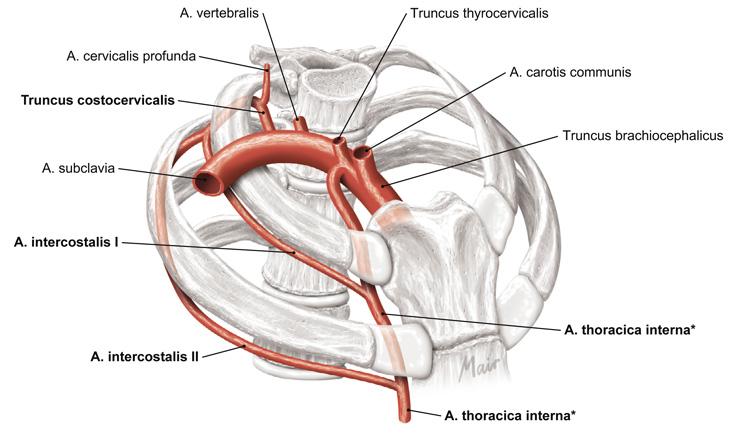

Fig 3.14: a. subclavia - zijtakken

glandula thyroidea = schildklier (groen) rib I tuberculum m. scalenus anterior v subclavia dextra -

truncus brachiocephalicus

a carotis communis (ACC) -

a subclavia dextra

a vertebralis (naar foramen transversarium C6-C2, a. basilaris) -

truncus thyrocervicalis

a thoracica interna = a. mammaria (langs sternum) -

truncus costocervicalis (posterieur)